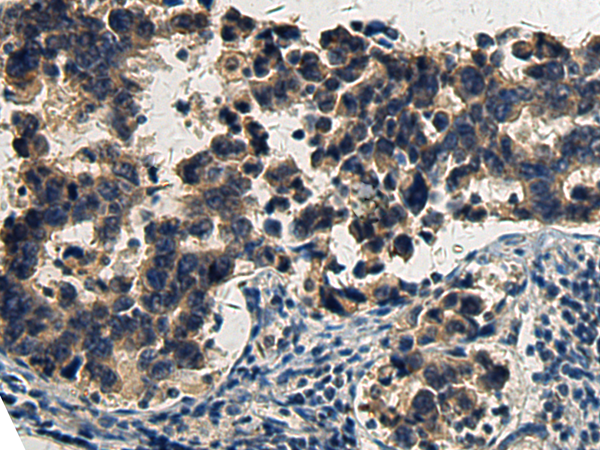

分类: 科研抗体货号: P11225别名: BOKL; BCL2L9应用: IHC反应种属: Human, Mouse, Rat